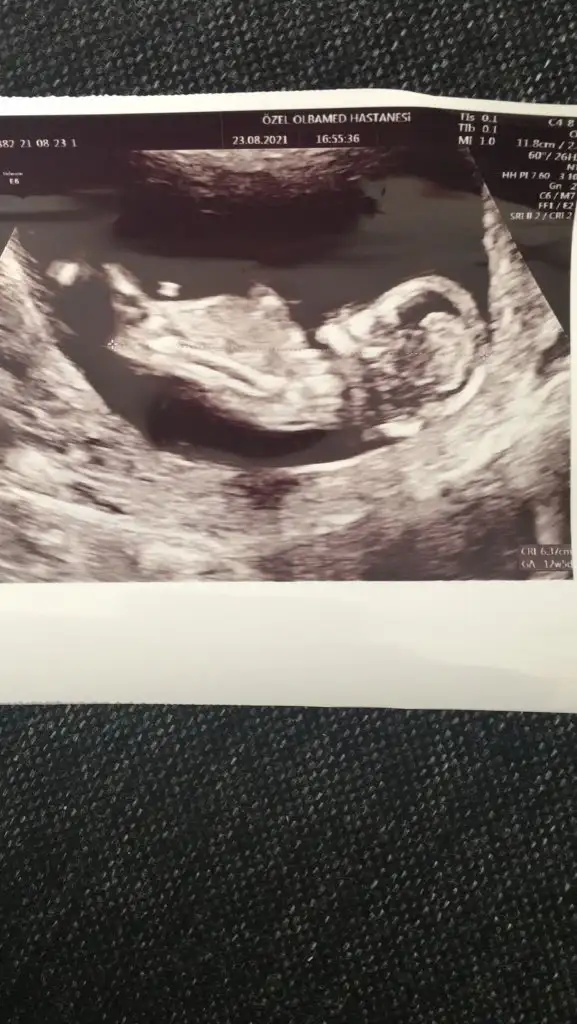

Erkek ve kız için 11 + 12+ yada 13 hafta usg görüntüsü olmalı açıklamalar asagıda yazıyorrabbim herkesin gönlüne göre nasip etsin inşallah .. ecmain

[/B]Eki Görüntüle 473828 gordugunuz gibi ust taraftaki simgedende anlasildigi gibi eger cikinti paralel ise kiz

yok 30°lik bir aciyla yukari dogru bakiyorsa %99 oglunuz olacak demektir simdi bi kac ornek resimler daha koyacagim kiziminkide dahil

Eki Görüntüle 473831 simdi burada cikintilara bakin eger bel popo cizgisine paralel ise kiz

yok 30 derecelik bir aciyla yukari bakiyorsa erkek

11 12 13 haftalar olmalı şimdilik kız yönünde ama yanıltabilir dediğim gibi tekrar USG paylasin